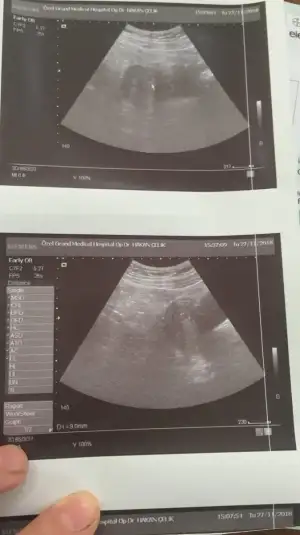

Merhaba kizlar bu gün kesem gözüktü 4+6 dedi doktor burdan biri kese hangi taraftaysa ona göre cinsiyet tahmin ediyordu kimdi o

• 48E4F86F-D574-4D35-9ABA-B5A04B8A0741.webp

48E4F86F-D574-4D35-9ABA-B5A04B8A0741.webp

29,4 KB · Görüntüleme: 53